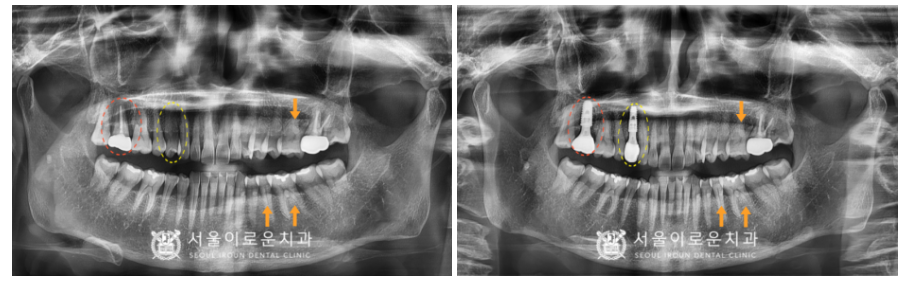

그리고 임플란트 식립 후 2달 반 후에

뼈와 임플란트가 단단하게

결합이 잘 되었는지 확인하는

osstell beacon이라는 장비를 이용하여

골유착정도(isq)를 측정하였고,

안정 값을 확인한 뒤

보철 과정까지 마무리해 드렸습니다.

오른쪽 위 작은 어금니(#14) 부위의

임플란트 과정이 마무리되고 얼마 뒤

환.자분께서 첫 번째 큰 어금니 부위(#17)의

통.증을 호소하시며

다시 내원해 주셨는데요. (ㅠㅠ)

이전에 설명드렸던 대로

발치 후 임플란트를

진행하기로 계획하였습니다.

아무래도 염증이 심했던 부위라

발치 후 임플란트 즉시 식립은 어려워

염증을 깨끗하게 제거한 뒤

정기검진을 통해

발치 부위를 체크하였는데요.

주변 잇몸과 뼈가

잘 차오른 것을 확인한 뒤

발치 후 3달이 되는 시점에

뼈이식을 동반하여 임플란트를

식립해 드렸습니다.

임플란트 식립 후 2달 반 후에

골유착 정도(isq)를 측정하여

보철물 과정을 진행하였습니다.

2개의 임플란트와 더불어

치경부 마모증 부위엔

레진치료를 모두 종결하였습니다!

✅ 전 > 후 ✅

(2024.02.22 ㅡ> 2024.08.02)